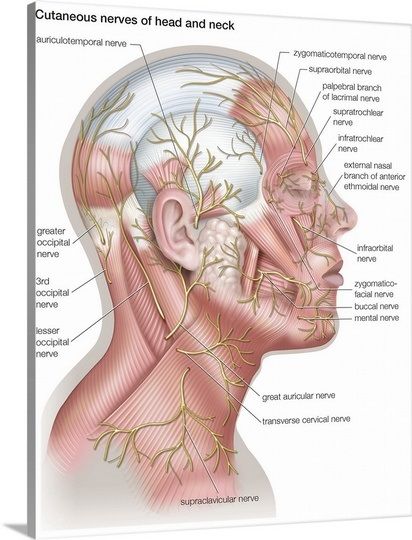

The human body is incredibly complex. Make it understandable with a diagram from Encyclopaedia Britannica. https://t.co/nqXY2hnYSW